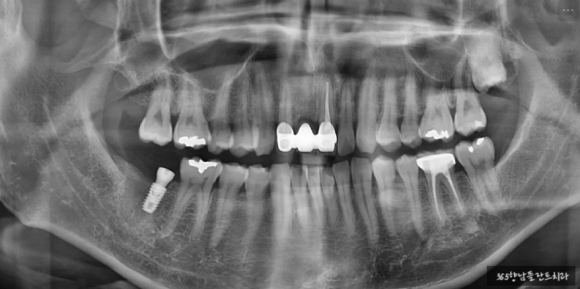

24.03.02 치료 전

24.06.21 식립 후

24.10.18 치료 완료

인공치아 뿌리 식립 후 잇몸뼈와 충분히 고정되는 것을 기다린 후 기둥을 세우고 신경관 임플란트 치료를 완료하였습니다.